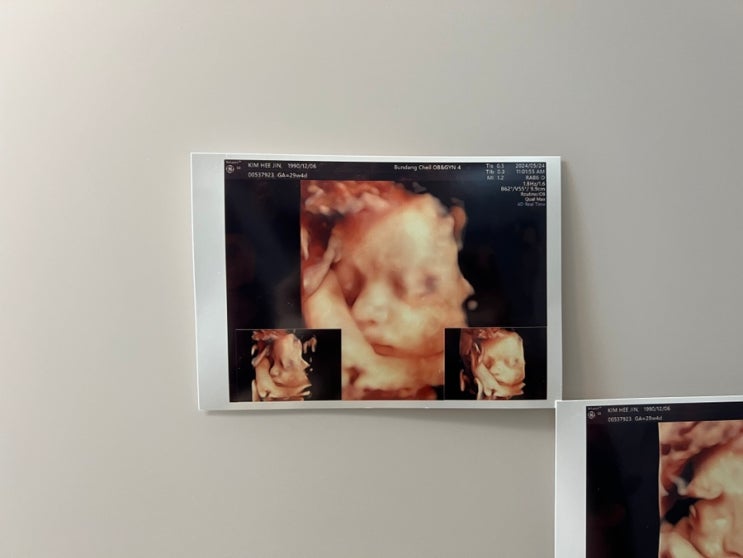

임신 35주차에 알게 된 제왕절개 분만일 결정 방법. 38주 vs 39주

내 아기 분만을 제왕절개로 결정한 임산부라면 무조건 고민하는 ‘분만 주수와 분만일’ 자식 생일을 내가 ...